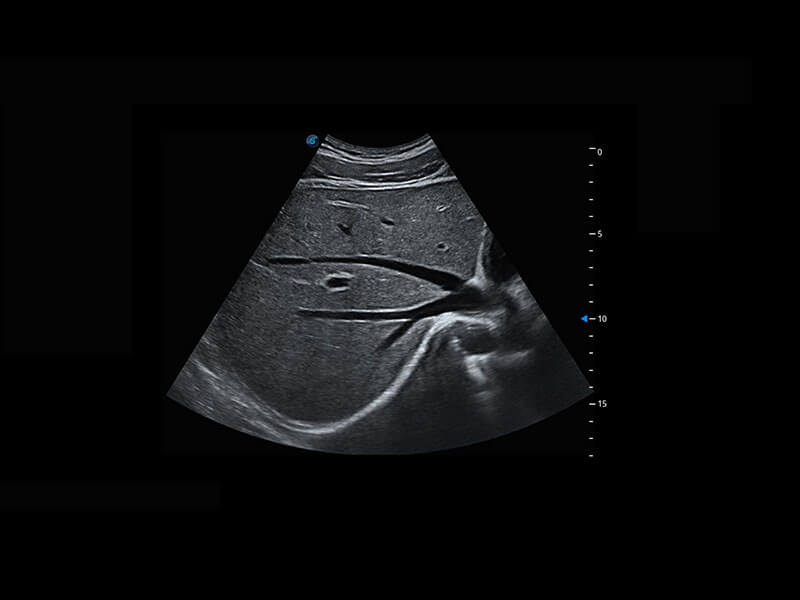

盆底超声

P60为盆底超声检查提供应用方案,多种腔内及腹部容积探头提供从二维、三维到四维的优异图像品质,实时快速三维容积数据获取,专业的测量工具包等人性化设计,为超声医生诊断提供有力保障。